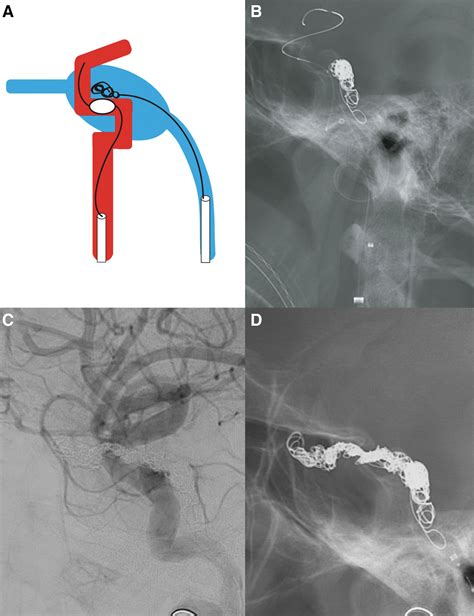

The goal of treating a Carotid Cavernous Fistula is to close the fistula while preserving the flow of blood through the internal carotid artery. In many cases, endovascular surgery is the preferred approach. During this minimally invasive procedure, a surgeon navigates a microcatheter through the blood vessels to the site of the fistula.

Therapeutic options usually include:

• Detachable Balloons: Used to occlude the fistula while keeping the artery open.

• Coils: Platinum coils are inserted to induce clotting and block the abnormal blood flow.

• Liquid Embolic Agents: Materials like glue or Onyx are used to permanently seal the connection.

In rare or complex scenarios, open neurosurgery or sacrifice of the parent artery may be necessary if endovascular techniques are not feasible.